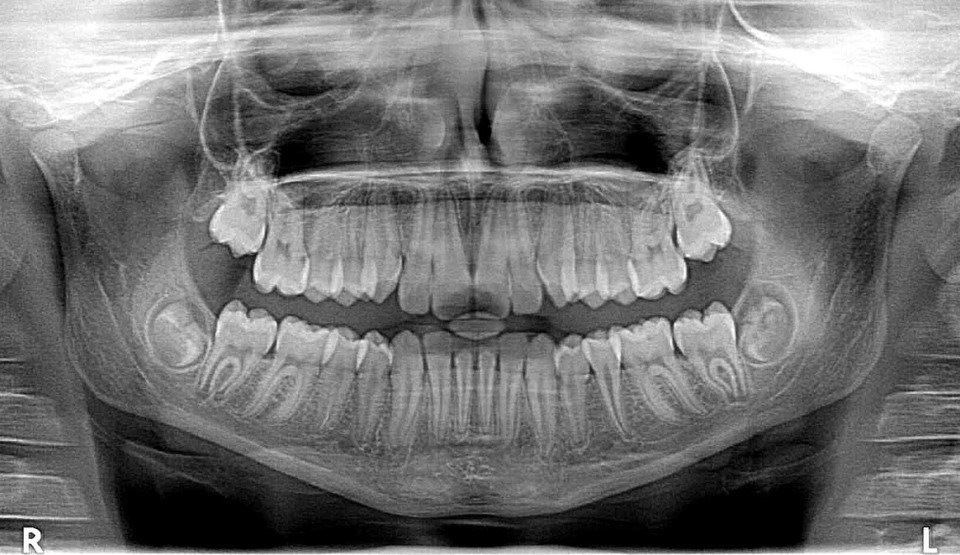

Copilul de 4 ani, care a intrat în comă, după ce a fost anesteziat la stomatologie, în Piteşti, a murit, miercuri, la Spitalul „Grigore Alexandrescu”, după un stop cardio-respirator, au anunţat reprezentanţii unităţii medicale.

Copilul de patru ani intrase în comă în urma unei anestezii generale efectuată la dentist. Miercuri după-amiaza el era în moarte cerebrală, ţinut în viaţă doar de aparate, au precizat, pentru Mediafax, medicii Spitalului „Grigore Alexandrescu”.